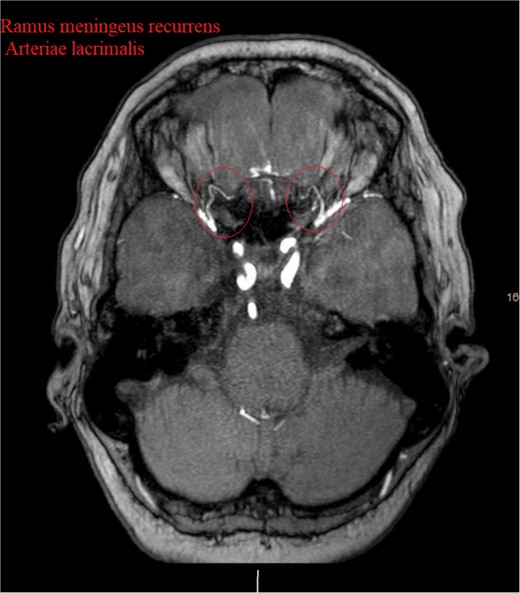

Brain CT imaging unveiled a hypodense fronto-basal lesion measuring 9–10 cm with finger-shaped perifocal edema (Fig. 1). contrast-enhanced cMRI provided more precise dimensions of the lesion (52 x 41 x 82 mm), demonstrating mild compression on both lateral ventricles and posterior displacement of the right middle cerebral artery and both anterior cerebral arteries without signs of hydrocephalus or perfusion disturbances (Fig. 1) and the bilateral COF anastomoses (Fig. 2) .

Showing the CT imaging with a hypodense fronto-basal lesion with finger-shaped perifocal edema and the T1-weighted MRI image with homogenous contrast-enhancing frontobasal lesion demonstrating mild compression on both lateral ventricles and posterior displacement of the right middle cerebral artery (MCA) without evidence of hydrocephalus.

Show the MRA with the bilateral anastomotic branch of the lacrimal artery with the middle meningeal artery.